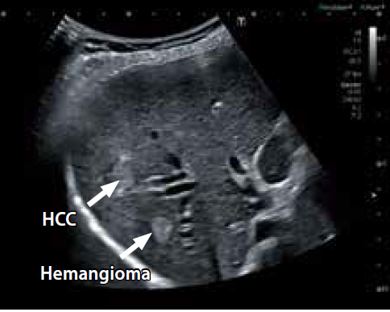

Вогнищеві ураження печінки з використанням CEUS

На рисунку 4 показано сірошкальне зображення (а) і ультразвукове зображення з контрастним підсиленням (CEUS) (б) гепатоцелюлярної карциноми (ГЦК) і гемангіоми печінки, отримане за допомогою датчика PVI-475BX. Використання CEUS у глибинних ділянках може бути складним через зниження чутливості. Також може бути важко охарактеризувати явище раннього вимивання в пізній судинній фазі, що спостерігається при недиференційованій ГЦК.

Крім того, при використанні CEUS для розмежування пухлин, розташованих в глибинних ділянках, оператори часто вдаються до збільшення підсилення, щоб компенсувати затухання, однак це призведе до збільшення сигналів від тканин і вплине на правильність аналізу контрастних ультразвукових зображень. Ультраширокосмуговий датчик має високу чутливість до контрастного ультразвуку і забезпечує однорідні зображення навіть у глибинних ділянках. Явище раннього вимивання, яке виявляється тільки при ГЦК, підвищує точність діагностики.

a) Відтінки сірого

б) CEUS

Рисунок 4. Сірошкальне зображення (а) та CEUS-зображення (б) гепатоцелюлярної карциноми (ГЦК) та гемангіоми печінки.